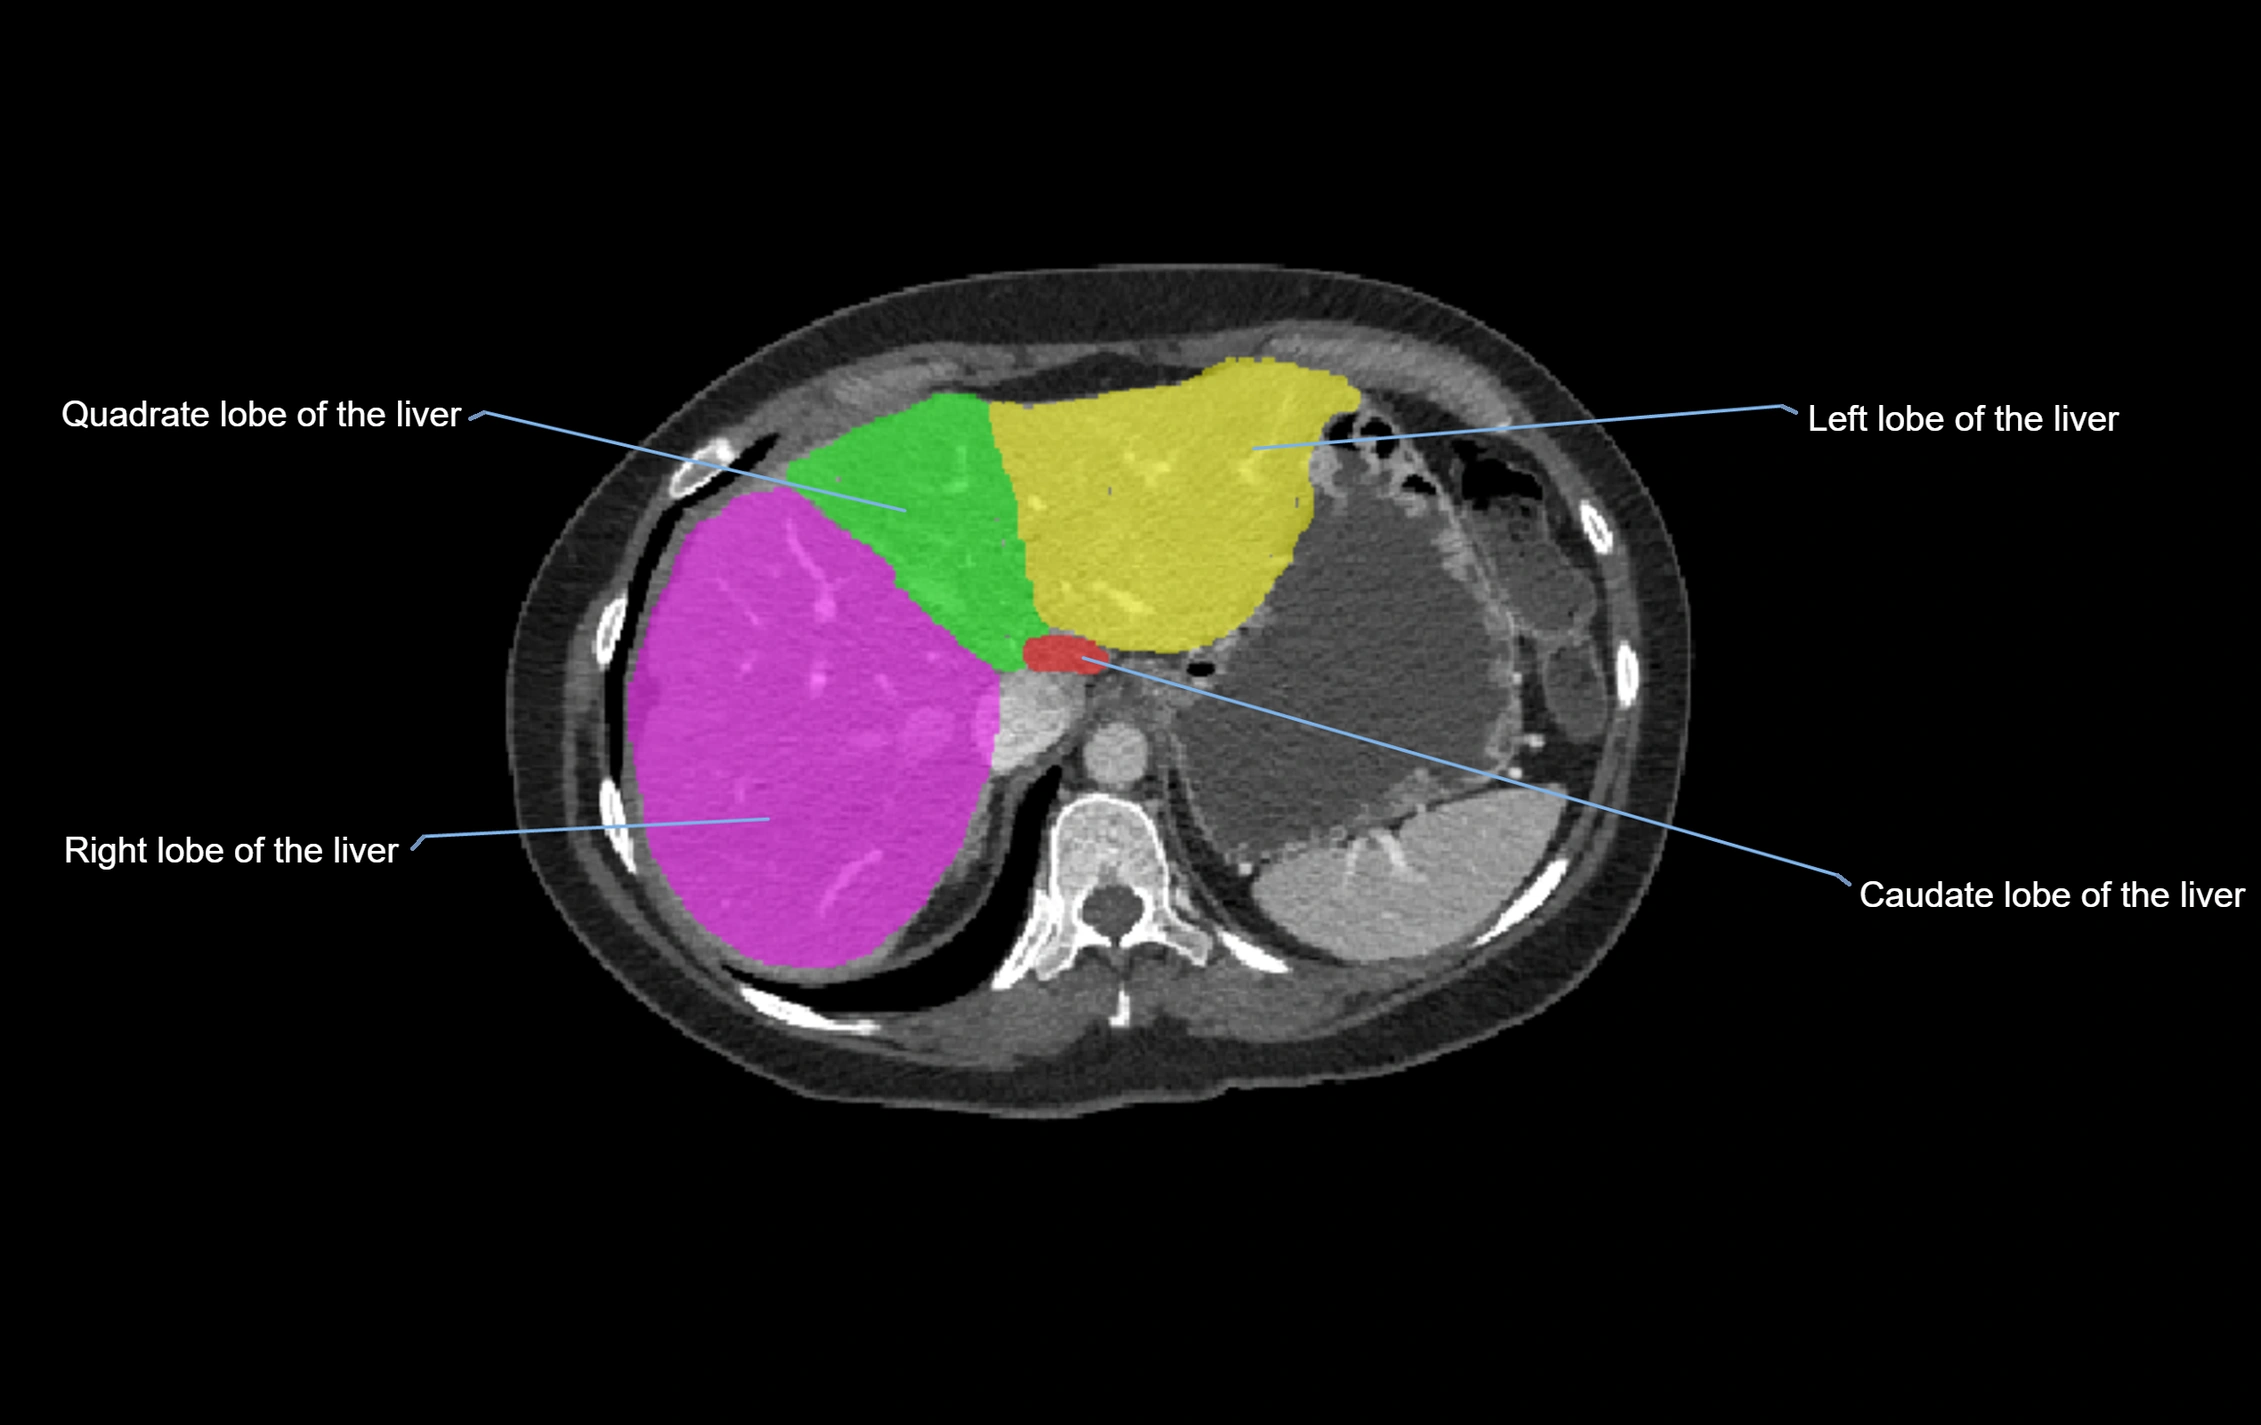

The caudate lobe of the liver is a distinct anatomical subdivision of the liver, designated as segment I in Couinaud’s classification. It lies on the posterior surface of the liver, between the fissure for the ligamentum venosum (left boundary) and the groove for the inferior vena cava (IVC) (right boundary). Superiorly, it is related to the posterior liver surface, and inferiorly it is separated from the left lobe by the porta hepatis.

CT Appearance

CT Pre-Contrast:

• Caudate lobe appears as a soft-tissue density, isodense to the rest of the liver

• Enlargement may be appreciated in cirrhosis or Budd–Chiari syndrome

CT Post-Contrast:

• Homogeneous enhancement in the portal venous phase, similar to rest of liver

• Independent venous drainage into the IVC may be visualized

CT Venous Phase (functional significance):

• Caudate lobe often enhances relatively more than other lobes in Budd–Chiari syndrome, due to preserved venous outflow

CT Image

image